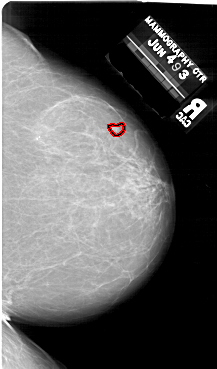

A_1640_1.RIGHT_CC

RIGHT_CC LINES 6631 PIXELS_PER_LINE 3901 BITS_PER_PIXEL 12 RESOLUTION 43.5 OVERLAY

FILE: A_1640_1.RIGHT_CC.OVERLAY

TOTAL_ABNORMALITIES 1

ABNORMALITY 1

LESION_TYPE MASS SHAPE IRREGULAR MARGINS ILL_DEFINED

ASSESSMENT 5

SUBTLETY 3

PATHOLOGY MALIGNANT

TOTAL_OUTLINES 1

BOUNDARY